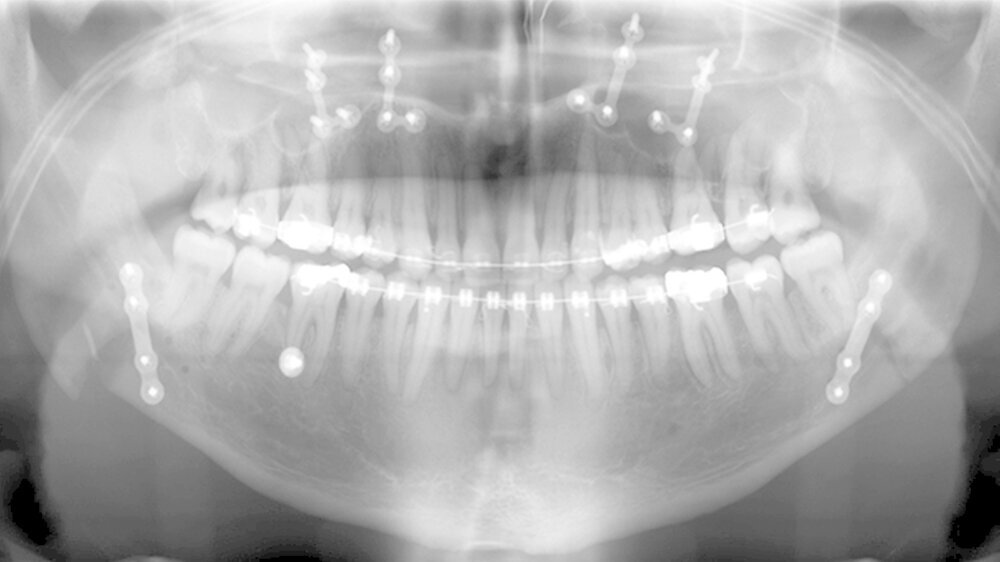

Der Patient stellte sich erstmals 2010 in der Stuttgarter MKG-Spezialsprechstunde vor. Im ersten Schritt wurde der Tumor an der Hirnanhangdrüse über die Nase entfernt. In interdisziplinärer Zusammenarbeit mit einem Fachzahnarzt für Kieferorthopädie wurden im ersten Behandlungsabschnitt die Zahnbögen ausgeformt. Um den Oberkiefer in der Breite zu dehnen, führten die Stuttgarter Zahnärzte im Oktober 2012 eine chirurgisch unterstützte Gaumennahterweiterung durch.

Nach dreidimensionaler Planung im zahntechnischen Labor, in dem die Bissschlüssel konventionell hergestellt wurden, wurden dann ein Jahr später beide Kiefer operativ mobilisiert. Hierzu wurde von einem Schnitt im Mund der Oberkieferknochen freigelegt.

Mit einer Säge wurde ein gezielter Knochenschnitt durchgeführt. Nach der Präparation wurde der zahntragende Abschnitt des Oberkiefers vom restlichen Gesichtsschädel gelöst. Erst wurde die Bisssituation anhand des Bissschlüssels exakt eingestellt, dann mit 2 mm dicken Osteosyntheseplatten aus Titan der Knochen in der neuen Position mithilfe von Titanschrauben fixiert.

Im Unterkiefer erfolgte dann die Schnittführung im Zahnfleisch hinter dem letzten Backenzahn beidseits. Nun wurde der Unterkiefer mit spezieller Technik durchtrennt um die zahntragende Basis vom gelenktragenden Knochenabschnitt des Unterkiefers zu verschieben. Bei der Präparationwurde der im Unterkieferknochen verlaufende Gefühlsnerv der Unterlippe sorgfältig geschont.

Die neue Position wurde mit einem zweiten Bissschlüssel, der die endgültige Bisssituation einstellt,zugeordnet und mit Osteosyntheseplatten und -schrauben gesichert. Die Operation ging mit einem stationären Aufenthalt von nur fünf Tagen einher.